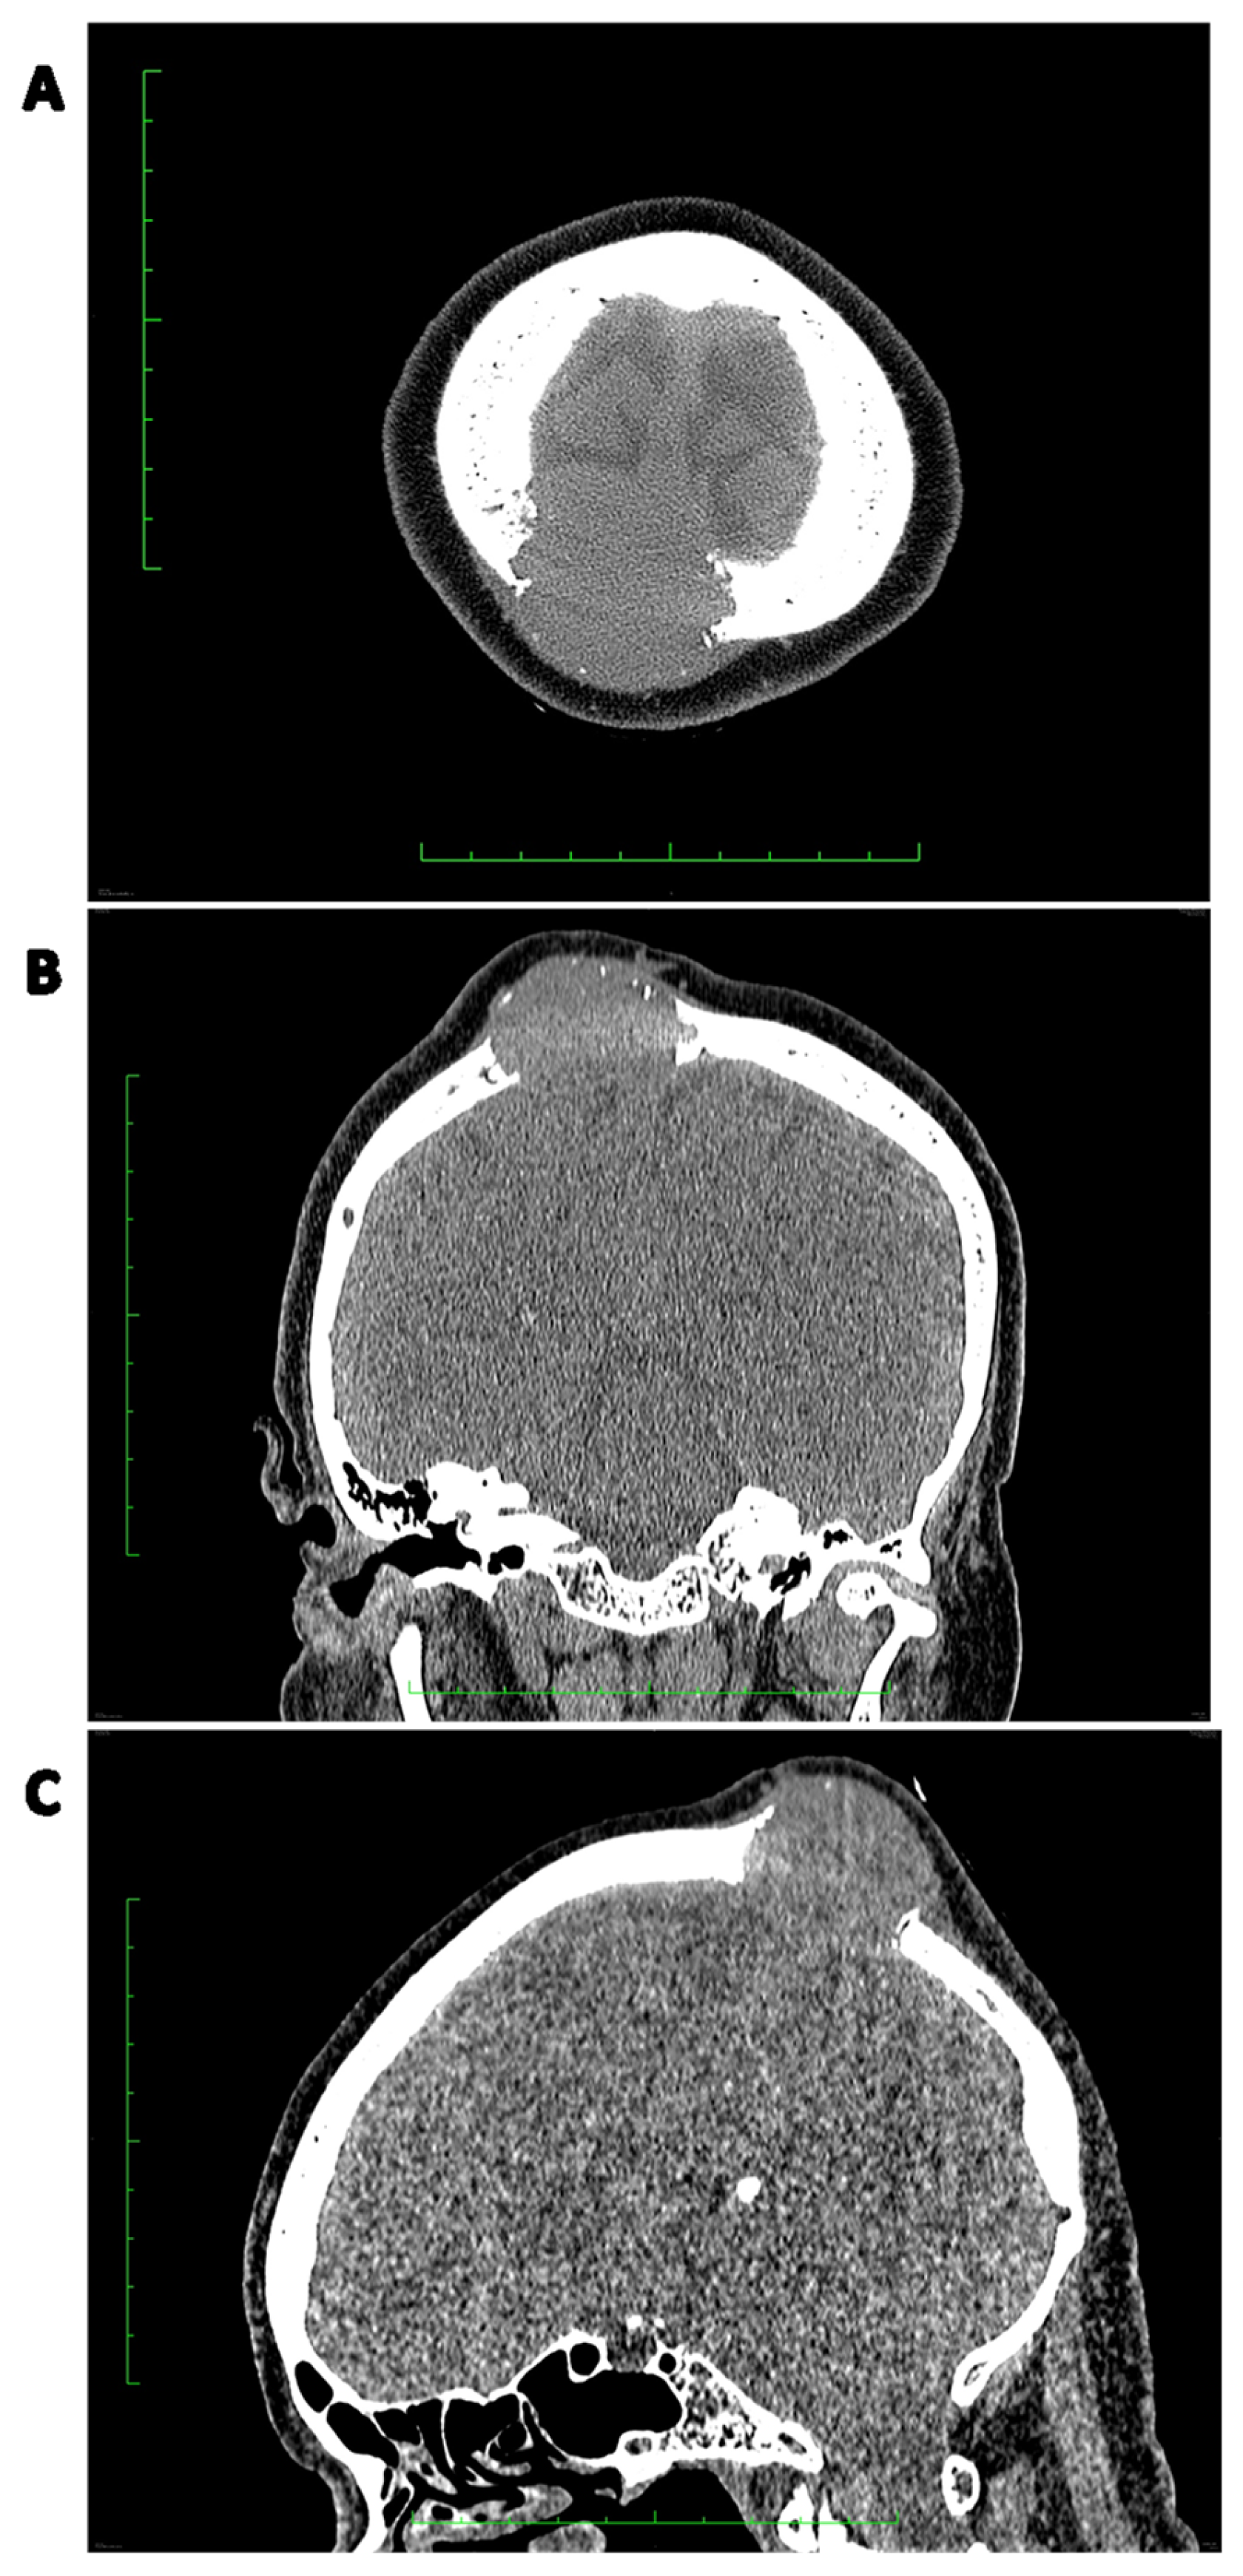

Figure 7.

Preoperative radiotherapy for a marginally resectable pelvic solitary fibrous tumor.

Moreover, in the case of mediastinal SFTs with external invasion, postoperative radiotherapy may provide a substantial benefit in local control [174]. Some studies report a regain of resectability after preoperative radiotherapy [176,177]. Therefore, SFTs may not be as radioresistant as other soft tissue sarcomas. An example of preoperative radiotherapy in a marginally resectable pelvic SFT is presented in Figure 4. The patient received 50 Gy in 25 fractions.